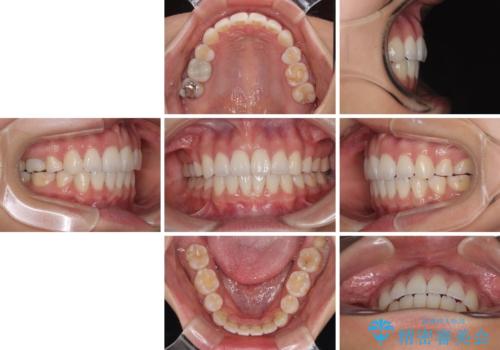

唇を閉じて眠れない ワイヤー装置での抜歯矯正で口元をスッキリと

- 前歯が突出して、眠るときに口が開いてしまうことを気にして来院された患者様です。

横から見た際の口元の飛び出した印象も改善したいとのことで、上下左右の第一小臼歯4本を抜歯し、ワイヤー装置にて抜歯矯正を行うこととしました。

舌の突出癖改善のためのトレーニングをしっかりと実践してくださり、2年強の治療期間でしっかりと仕上げることができました。